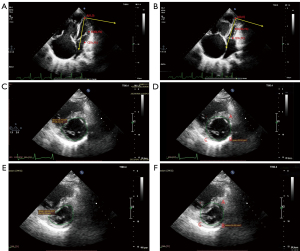

The imaging data are digitally stored for subsequent offline analysis. The ratios of left ventricular volume change and left ventricular area change are derived from the same offline image of the respective patient. The approach for assessing the ratio of left ventricular volume change involves measuring end-diastolic and end-systolic volumes via Simpson’s method in the four-chamber view at the apex of the heart, as illustrated in Figure 2. After the aforementioned images were obtained, three distinct points were delineated on the lateral wall of the left ventricle at the apex (A), middle (B), and base (C) positions. The apex served as the origin, and the longitudinal axis of the left ventricle was designated the horizontal axis for recording the X and Y coordinates of points A, B, and C via ImageJ (https://imagej.nih.gov/ij) (17). It can also be directly measured via an Echo machine during a patient’s examination. The three points are used to compute the quadratic equation y = f(x) = ax2 + bx + c with three variables, which are rotated once, and the volume integral of a revolving object is employed to determine the unexpanded LV standard volume: . This volume contrasts with the LV volume obtained through Simpson’s method, distinguishing between actual and standard measurements. In addition, we used a new measurement method to calculate the ratio of the change in the LV area in the short-axis section: the papillary muscle in the short-axis plane of the LV approximates a circle; thus, in the maximum and minimum periods of the LV, we used software to measure the actual area of the LV along the dense myocardium at https://www.radiantviewer.com remember. Then, the standard area of the LV before compression was measured at three positions in the LV lateral wall [anterior (A), middle (B), and posterior (C)] and compared with the actual area, that is, the actual/standard area. At the beginning of our investigation, we conducted a preliminary study to calculate the aforementioned values for healthy individuals and performed a statistical analysis to compare these actual values with standard indicators. No statistically significant differences were observed (P>0.05). The actual values closely resembled the standard values, as illustrated in Table 1. Furthermore, in line with prior research, we employed normalized curvature to assess septal curvature (13). The method used to compute the LVEI was akin to that outlined by Ryan et al. (18).